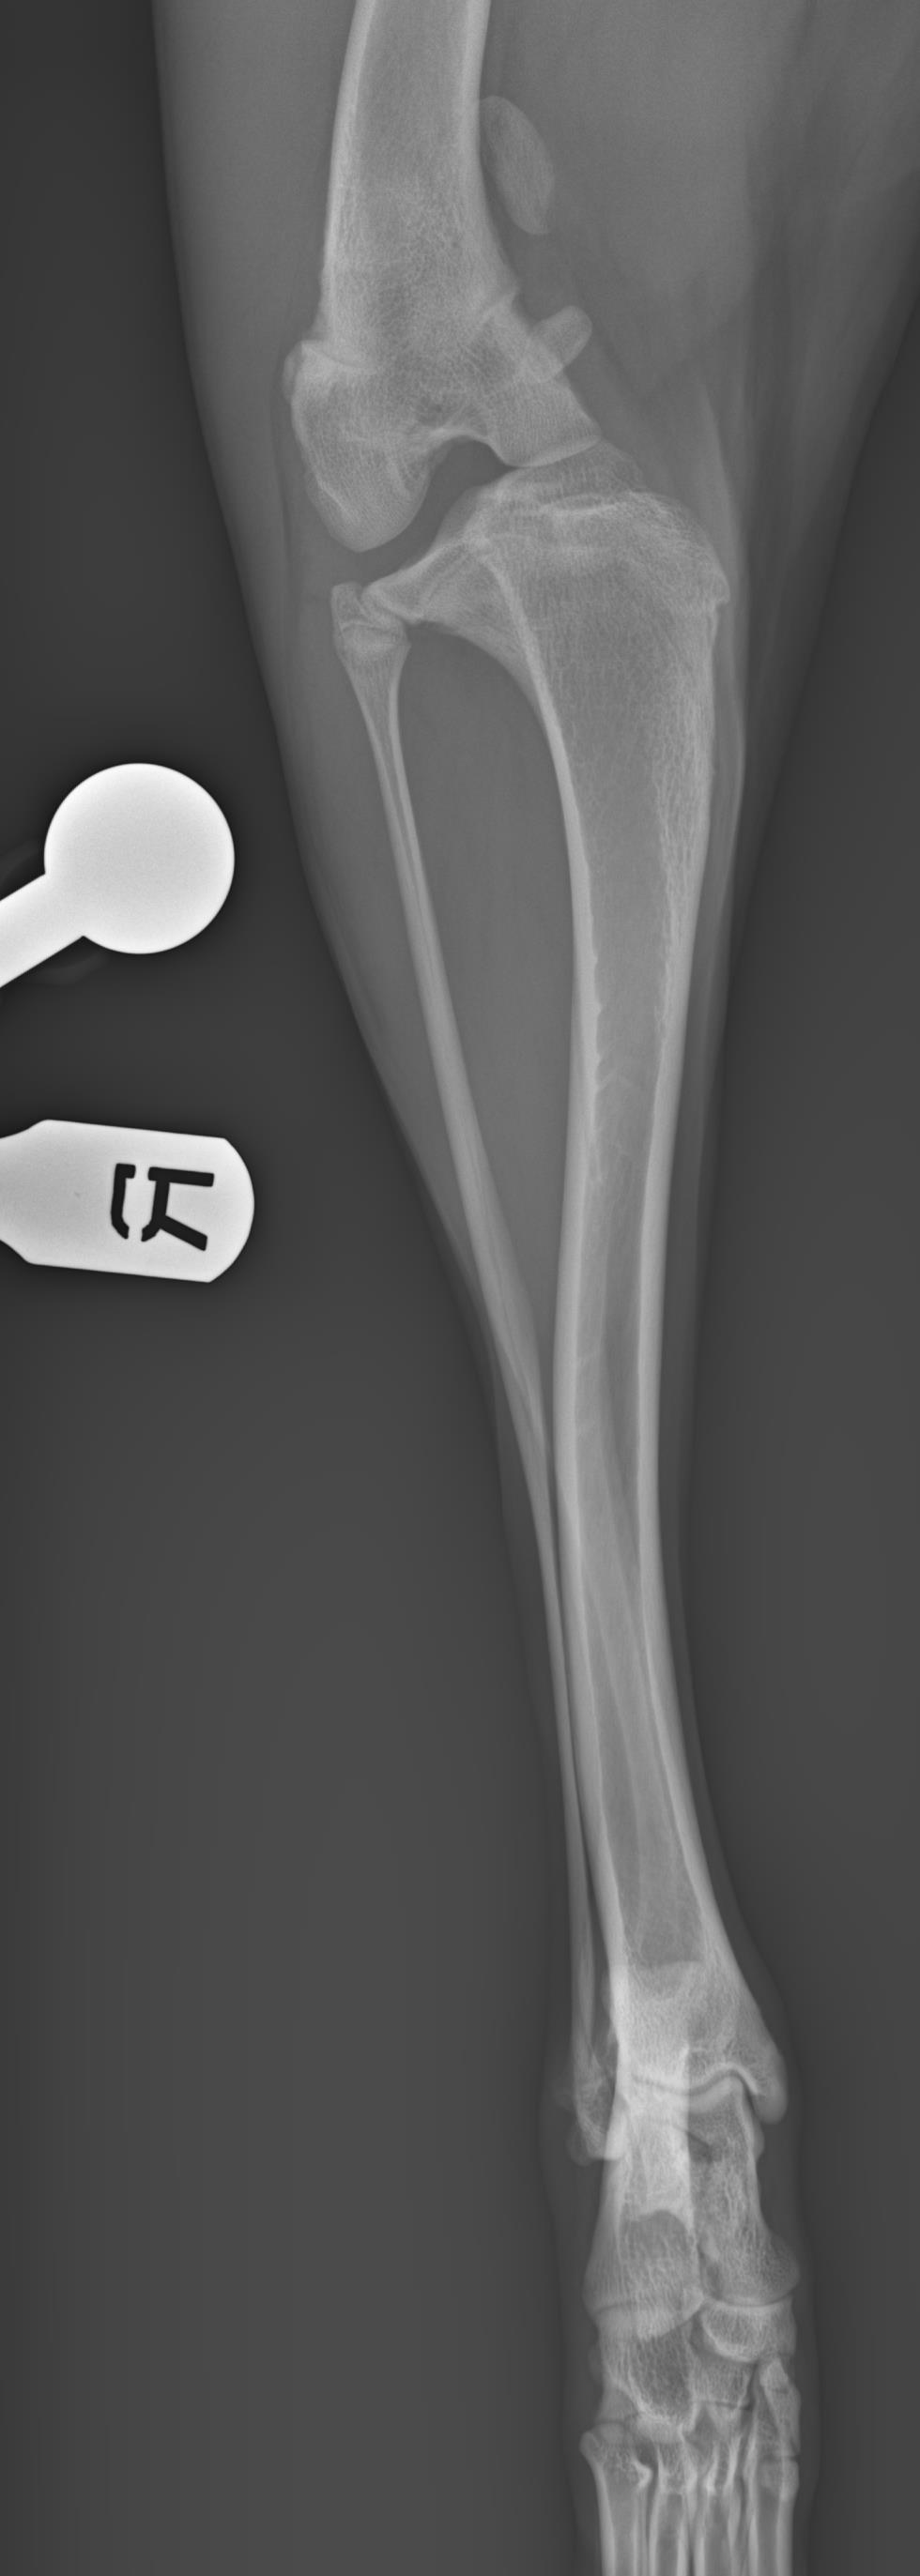

Edit Project Cartesian Medical - New Project Form *required What service are you interested in?* Virtual surgical planning consultation 3D printed services Research services Teaching assets What is the level of urgency for this case?* Elective/Non-urgent Urgent (Cartesian representative will reply within 24 hours) Project information: Tell us a bit about your project (scope, goals, etc)* Example: I have a 1 year old sheltie with bilateral short radius syndrome with subluxation of the left elbow. I took a CT scan and would like a model printed of the left radius ulna through mid-humerus to plan surgical correction. I am interested in having custom drill guides created as well. Ideally surgery would be scheduled in the next month. 3 year GSH bilateral grade 4 MPL with deformities of tibia and femur Patient/Project Name* (example: Buddy’s left elbow) Patient weight (kg) - if applicable Patient date of birth - if applicable Patient breed/species - if applicable Diagnostics performed?* None (No problem! Ask us to send over positioning and calibration guides) Radiographs CT MRI File: *Please send downloadable links to imaging or other information to info@cartesianmedical.com Submit